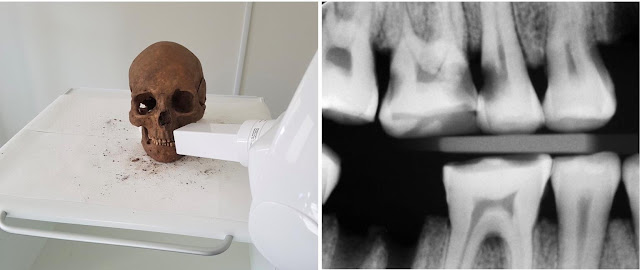

Ερευνητές από Πανεπιστήμιο του Γκέτεμποργκ στη Σουηδία, μελέτησαν 3.293 δόντια από 171 κρανία Βίκινγκ, τόσο ενηλίκων όσο και παιδιών. Πραγματοποιήθηκαν σύγχρονες οδοντιατρικές εξετάσεις και αποκαλύφθηκε πως οι Σκανδιναβοί δεν άφηναν τα δόντια τους να χαλάνε.

Τα δόντια χρονολογίας 10ου με 12ου αιώνα μ.Χ, συλλέχθηκαν από τη γνωστή αρχαιολογική τοποθεσία Varnhem, της οποίας το έδαφος ευνοεί τη διατήρηση οστών και δοντιών.

| Σύγχρονος εξοπλισμός σάρωσης χρησιμοποιήθηκε για τη μελέτη των δοντιών. [Credit: Carolina Bertilsson/Henrik Lund] |

Το 13% των δοντιών των ενηλίκων, φαίνεται πως έπασχαν από τερηδόνα ή κοιλότητες στην επιφάνεια των ριζών. Η απώλεια δοντιών ήταν εκτεταμένη, με τους ενήλικες να χάνουν κατά μέσο όρο το 6% των δοντιών τους, εξαιρουμένων των φρονιμίτων. Στα δόντια παιδιών κάτω των 12 ετών δεν υπήρχαν σημάδια αλλοίωσης των δοντιών.

Υπάρχουν επίσης αποδείξεις θεραπειών, όπως προσπάθειες να συμπληρωθούν τα κενά των γομφίων, μάλλον για να παρασχεθεί κάποια ανακούφιση από τον πονόδοντο που προκαλούσαν οι μολύνσεις.

Είναι πολύ εντυπωσιακό, δε διαφέρουν πολύ από τις οδοντιατρικές θεραπείες που χρησιμοποιούμε σήμερα, όταν τρυπάμε το μολυσμένο δόντι. Οι Βίκινγκ φαίνεται πως είχαν γνώση για τα δόντια, αλλά δεν ξέρουμε αν πραγματοποιούσαν μόνοι τους αυτές τις επεμβάσεις ή είχαν βοήθεια.

Ακόμα ένα ενδιαφέρον εύρημα είναι πως μέχρι την ηλικία των 40, η απώλεια δοντιών ήταν πολύ μεγαλύτερο πρόβλημα για τους Βίκινγκ από την τερηδόνα.

Η έρευνα παρέχει νέες πληροφορίες για την υγιεινή των δοντιών των Βίκινγκ και δείχνει πως τα δόντια ήταν σημαντικό κομμάτι της κουλτούρας των Βίκινγκ. Αποδεικνύει επίσης πως η οδοντιατρική στην εποχή των Βίκινγκ ήταν πιο εξελιγμένη από αυτό που πιστεύαμε.